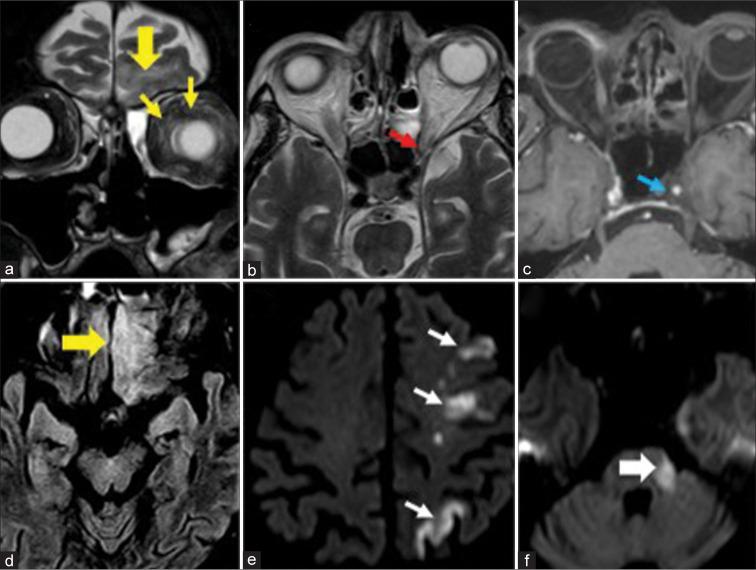

The most frequent MRI finding was T2 hypointensity in the sinonasal mucosa (94%) followed by mucosal necrosis/loss of contrast-enhancement (92.6%). Extrasinosal inflammation with or without necrosis in the pre-antral fat, retroantral fat, pterygopalatine fossa, and masticator space was seen in 91.1% of the cases. Extrasinosal spread was identified on MRI even when the computed tomography (CT) showed intact bone with normal extrasinosal density. Orbital involvement (72%) was in the form of contiguous spread from either the ethmoid or maxillary sinuses; the most frequent presentation being orbital cellulitis and necrosis, with some cases showing extension to the orbital apex (41%) and inflammation of the optic nerve (32%). A total of 22 patients showed involvement of the cavernous sinuses out of which 10 had sinus thrombosis and five patients had cavernous internal carotid artery involvement. Intracranial extension was seen both in the form of contiguous spread to the pachymeninges over the frontal and temporal lobes (25%) and intra-axial involvement in the form of cerebritis, abscesses, and infarcts (8.8%). Areas of blooming on SWI were noted within the areas of cerebritis and infarcts. Perineural spread of inflammation was seen along the mandibular nerves across foramen ovale in five patients and from the cisternal segment of trigeminal nerve to the root exit zone in pons in three patients. During follow-up, patients with disease progression showed involvement of the bones of skull base, osteomyelitis of the palate, alveolar process of maxilla, and zygoma. Persistent hyperenhancement in the post-operative bed after surgical debridement and resection was noted even in patients with stable disease.

Contrast-enhanced MRI must be performed in all patients with suspected AIFRS as non-contrast MRI fails to demonstrate tissue necrosis and CT fails to demonstrate extrasinosal disease across intact bony walls. Orbital apex, pterygopalatine fossa, and the cavernous sinuses form important pathways for disease spread to the skull base and intracranial compartment. While cerebritis, intracranial abscesses, and infarcts can be seen early in the disease due to the angioinvasive nature, perineural spread and skull base infiltration are seen 3-4 weeks after disease onset. Exaggerated soft-tissue enhancement in the post-operative bed after debridement can be a normal finding and must not be interpreted as disease progression.